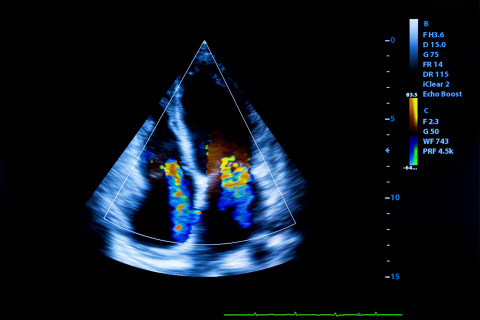

Human heart ultrasound image